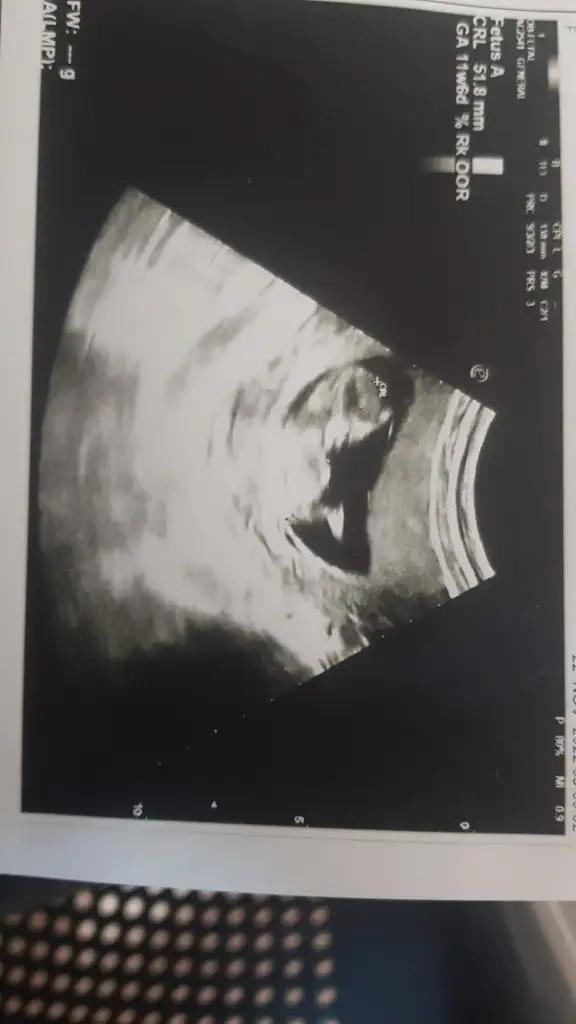

Karından 11+6💗💗

• IMG-20221122-WA0000.webp

IMG-20221122-WA0000.webp

14,9 KB · Görüntüleme: 98